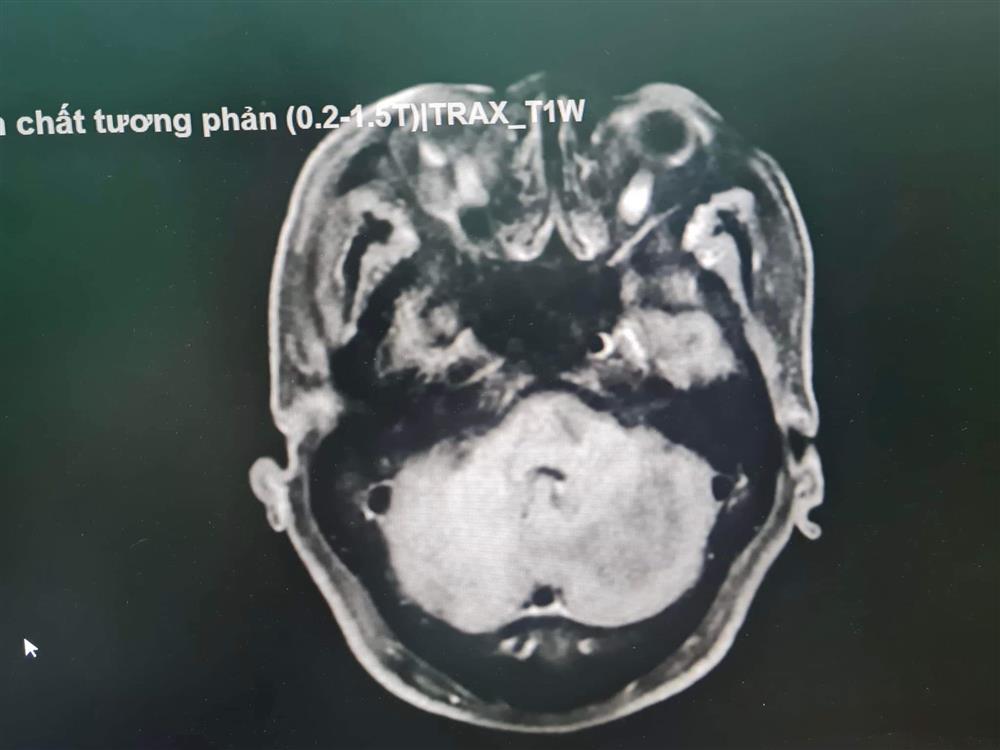

Thanh Hóa: Phẫu thuật thành công ca U não kích thước 3x2cm

Theo Ths.Bs. Lê Ngọc Biển, Trưởng Khoa Phẫu thuật Thần kinh -Lồng ngực (BV Đa khoa tỉnh Thanh Hoá), “đây là ca bệnh khó bởi khối u nằm ở vị trí sâu, phức tạp, đã xâm lấn vào thân não, gần với xoang ngang. Thêm vào đó, khi nhập viện, bệnh nhân đã bị phù não, chèn ép thần kinh và chèn ép thân não, không thể đi lại được…